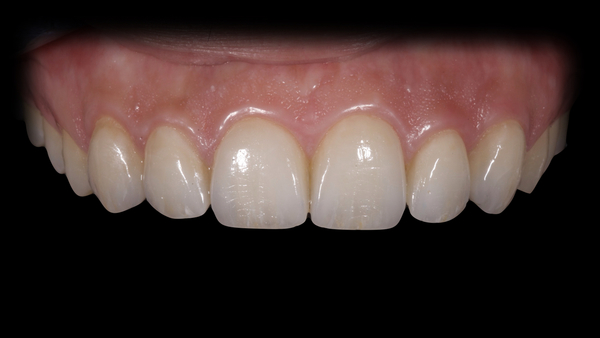

Dal progetto software veniva realizzato un prototipo che, messo in bocca, forniva utili informazioni sulla tecnica di preparazione mininvasiva. Venivano eseguite le preparazioni mininvasive sul gruppo frontale con tecnica di preparazione conservativa. Successivamente si eseguiva scansione intraorale delle preparazioni, associata per sottrazione al Digital Wax- Up. I restauri venivano realizzati con metodo DFAB (DWS Systems) utilizzando un composito ibrido caricato di vetroceramica IrixMax® DWS. I restauri ottenuti venivano adattati secondo la tecnica della Polishing Technique per la conservazione della qualità di superficie. I restauri erano cementati con la tecnica della cementazione adesiva Calibra® Veneer, impiegando cemento resinoso estetico foto-polimerizzante. Nella sequenza fotografica (Fig. 1- 11), la documentazione del caso clinico completo.

Fig. 10. I restauri appena cementati.